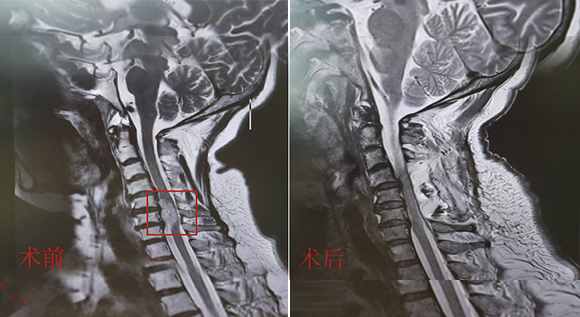

脊柱脊髓神经微创中心以微创技术为引领,以功能恢复为目标,主要治疗脊柱外伤、肿瘤、退行性病变、脊柱畸形等疾病。团队利用神经外科显微技术,结合神经内镜微创技术,对脊柱间盘变性疾病、颈腰椎管狭窄、颈腰椎间孔狭窄、颈腰椎间盘突出、颈腰椎体不稳、脊柱骨折、寰枢椎脱位、脊柱肿瘤、椎管内肿瘤、脊髓损伤、脊髓空洞、脊髓栓系等疾病进行高效、特色手术治疗,如颅颈交界区畸形寰枕减压内固定术、脊柱肿瘤全脊椎切除内固定术、微创椎管内肿瘤切除术、微创脊柱旁肿瘤切除术、寰枢椎脱位椎间融合内固定术、脊柱骨折微创经皮椎弓根钉内固定术、经椎间孔椎间融合内固定术(MIS—TLIF)等,最大程度降低脊柱脊髓手术创伤,具有创伤小、输血少、恢复快、口碑好,出院早等优势。